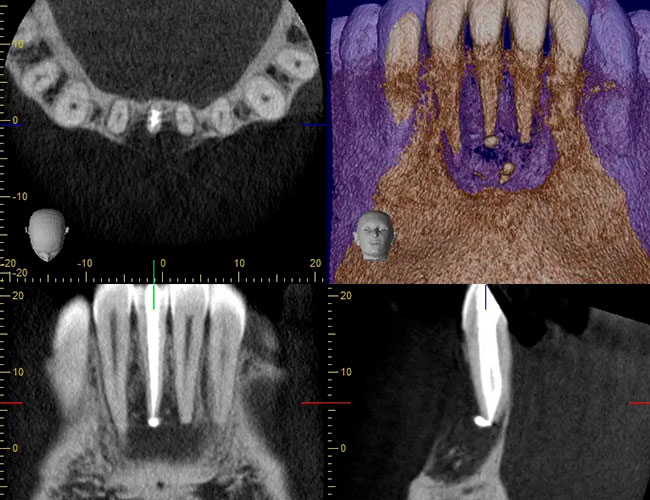

Hacemos una valoración clínica completa y, cuando aporta información decisiva, utilizamos radiografía 3D específica de alta resolución para ver el diente con el máximo detalle. Además, planificamos y revisamos el caso en monitores de grado médico, lo que nos ayuda a interpretar la imagen con más precisión y tomar decisiones más seguras antes de empezar.

Contamos con escáneres 3D, CBCT de alta resolución y planificación digital avanzada. Todo esto no es para presumir, sino para que tú tengas diagnósticos más precisos, tratamientos más seguros y una experiencia más cómoda, sin sorpresas.